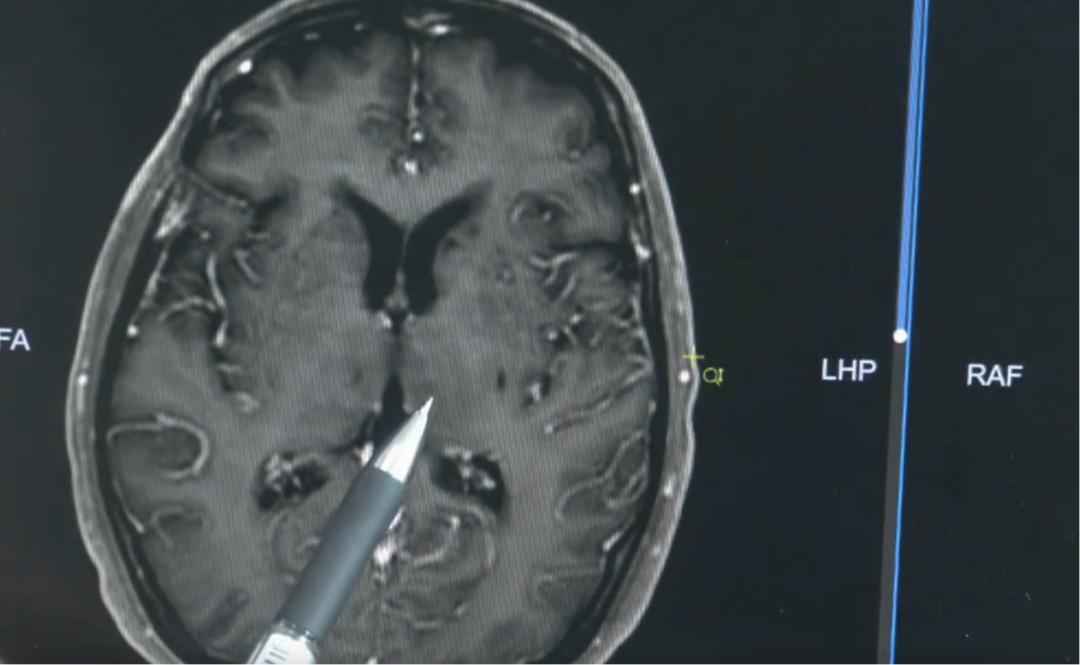

医生解释说:“正常的大脑,血脉屏障是完整的,造影剂没办法通过。但当脑子出现炎症,血脑屏障的通透性就会增加,白色的造影剂就会渗入脑子,这就提示我们脑子有炎症表现。”正是这种猪链球菌脑膜炎,影响了明叔大脑的听力区。